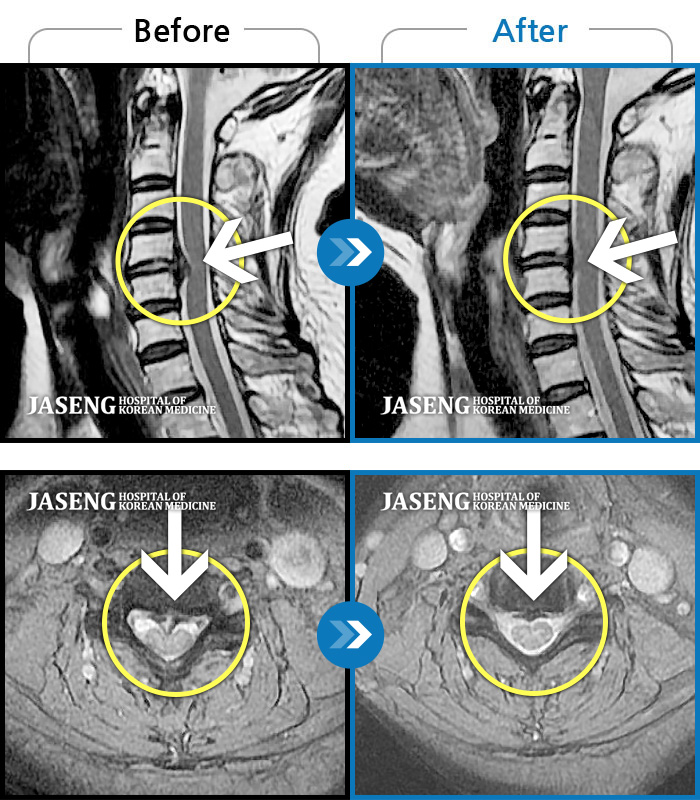

박정우 원장님 덕분에 목디스크가 많이 호전되었어요. 하지만 그 이유만으로 칭찬하는건 아닙니다. 세심한 치료와 좋은 실력,환자에 대한 배려가 조화를 이루는 참 좋은 의료인입니다.

양방만 고집하던 제가 한방치료에 대한 인식을 바꾸게 된 계기가 이분을 통해서입니다.